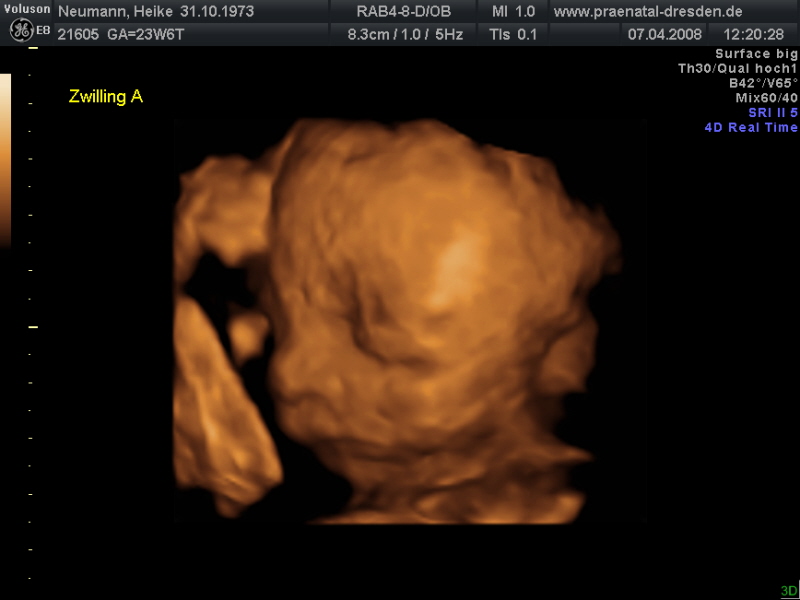

![]() |

| Aura 23.SSW | Josh 23.SSW |